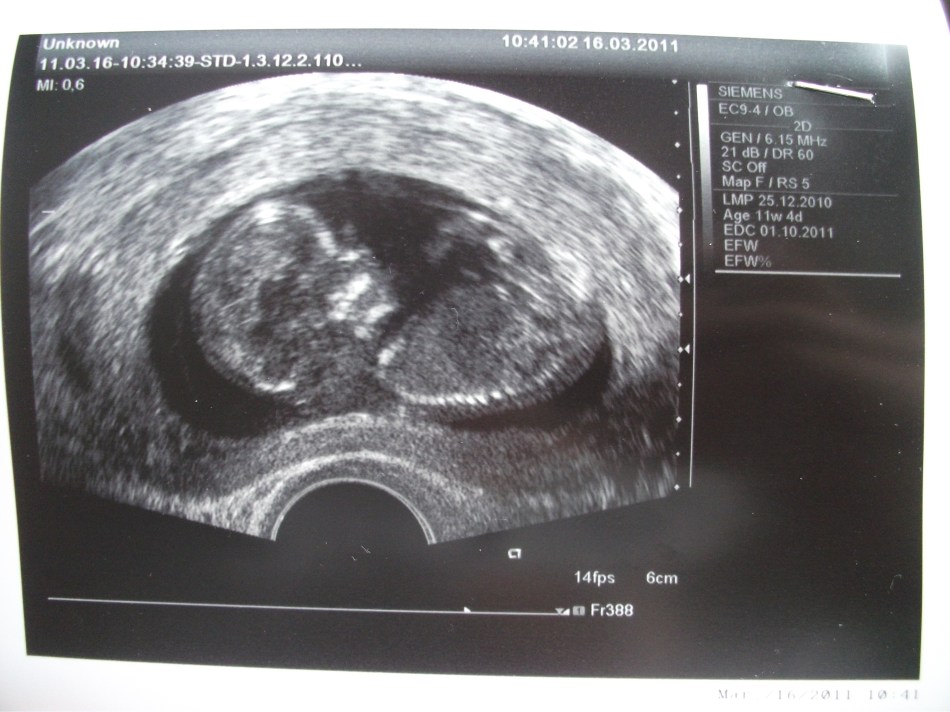

Katrina is pregnant!!! She is about 12 weeks along and so far everything seems normal. We are planning on having the baby here so we would ask for your thoughts during the next 6 months as we prepare.